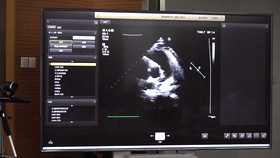

5G遠(yuǎn)程會診現(xiàn)場,西安國際醫(yī)學(xué)中心心內(nèi)科張衛(wèi)澤主任、超聲科陳姍姍主任打開4K高清顯示器,屏幕上立刻出現(xiàn)了商洛國際醫(yī)學(xué)中心的B超畫面,一位醫(yī)生正在為患者做心臟B超,隨著探頭的轉(zhuǎn)動,超聲機(jī)器上的畫面清晰可見,雖然兩家醫(yī)院相距一百多公里,但畫面流暢,沒一點(diǎn)拖沓。

“真的太棒了”張衛(wèi)澤表示,“沒有延時(shí)與卡頓,清晰的好像在一個(gè)房間內(nèi)進(jìn)行病歷討論”。陳姍姍非常興奮,直呼很震撼。她告訴筆者,“以前做遠(yuǎn)程會診,經(jīng)常遇到畫面和聲音不在一個(gè)頻道、畫面模糊等情況,遇到疑難病歷只能將影像拷下來回去研究,現(xiàn)在好了這些問題都將一次性解決?!?/span>